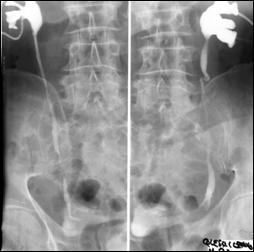

Diagnosticul diferential cu tuberculoza urogenitala

Vezica urinara are contururi greu delimitabile pe cistografie si pacientul are ureterohidronefroza bilaterala.

Figura 57. Vezica urinara mica |

Vezica urinara mica, scleroasa, cu rinichi drept unic chirurgical, uretero-hidronefroza gr I

Figura 59. Vezica urinara "crispata", cu ureterohidronefroza bilaterala. |